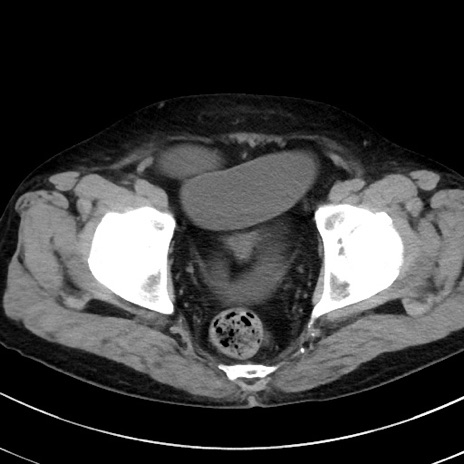

症例38(横断像)

【症例】70歳代 男性

【主訴】腹痛・嘔吐

【現病歴】昨晩より、嘔吐・腹痛あり。今朝になっても嘔吐あり。来院。

【既往歴】心臓バイパス手術、開腹胆摘、腸閉塞

【身体所見】BP 107/71mmHg、HR 116/min、腹部:平坦、軟、下腹部に軽度圧痛あり。反跳痛なし。

【データ】WBC 15100、CRP 0.32

冠状断像